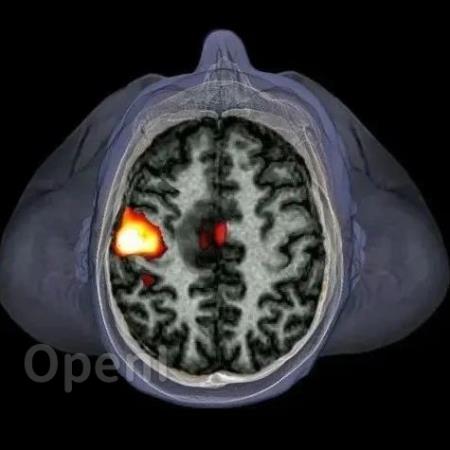

原标题:看见神经元活动:fMRI的进步让大脑成像更快更精细 | 《自然》长文